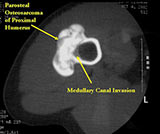

- Parosteal osteosarcomas that are present for prolonged periods of time may either have areas that become higher grade or dedifferentiate. Dedifferentiation refers to a portion of the tumor changing and becoming a high grade type of sarcoma. In addition, parosteal osteosarcomas that are present for a prolonged period of time can invade the bone (medullary canal) that it arose from. Tumors that have undergone dedifferentiation or invaded the underlying bone are more aggressive and have a higher risk of metastasizing (spreading). This is important to know for treatment purposes. Typically, low grade parosteal osteosarcomas are treated with surgery alone. Parosteal osteosarcomas with high grade areas may also be treated with chemotherapy in addition to surgery.

- There may be invasion of the medullary canal with long standing disease

- Useful for determining medullary invasion

- Can help discern areas that may be high grade

- If it has grown through the cortex, there may be an intramedullary component

- Metastases more common with medullary invasion, high grade components (grade 3) and dedifferentiation (grade 3 tumors)

- Many parosteal osteosarcomas with intramedullary extension are higher grade lesions or dedifferentiated tumors